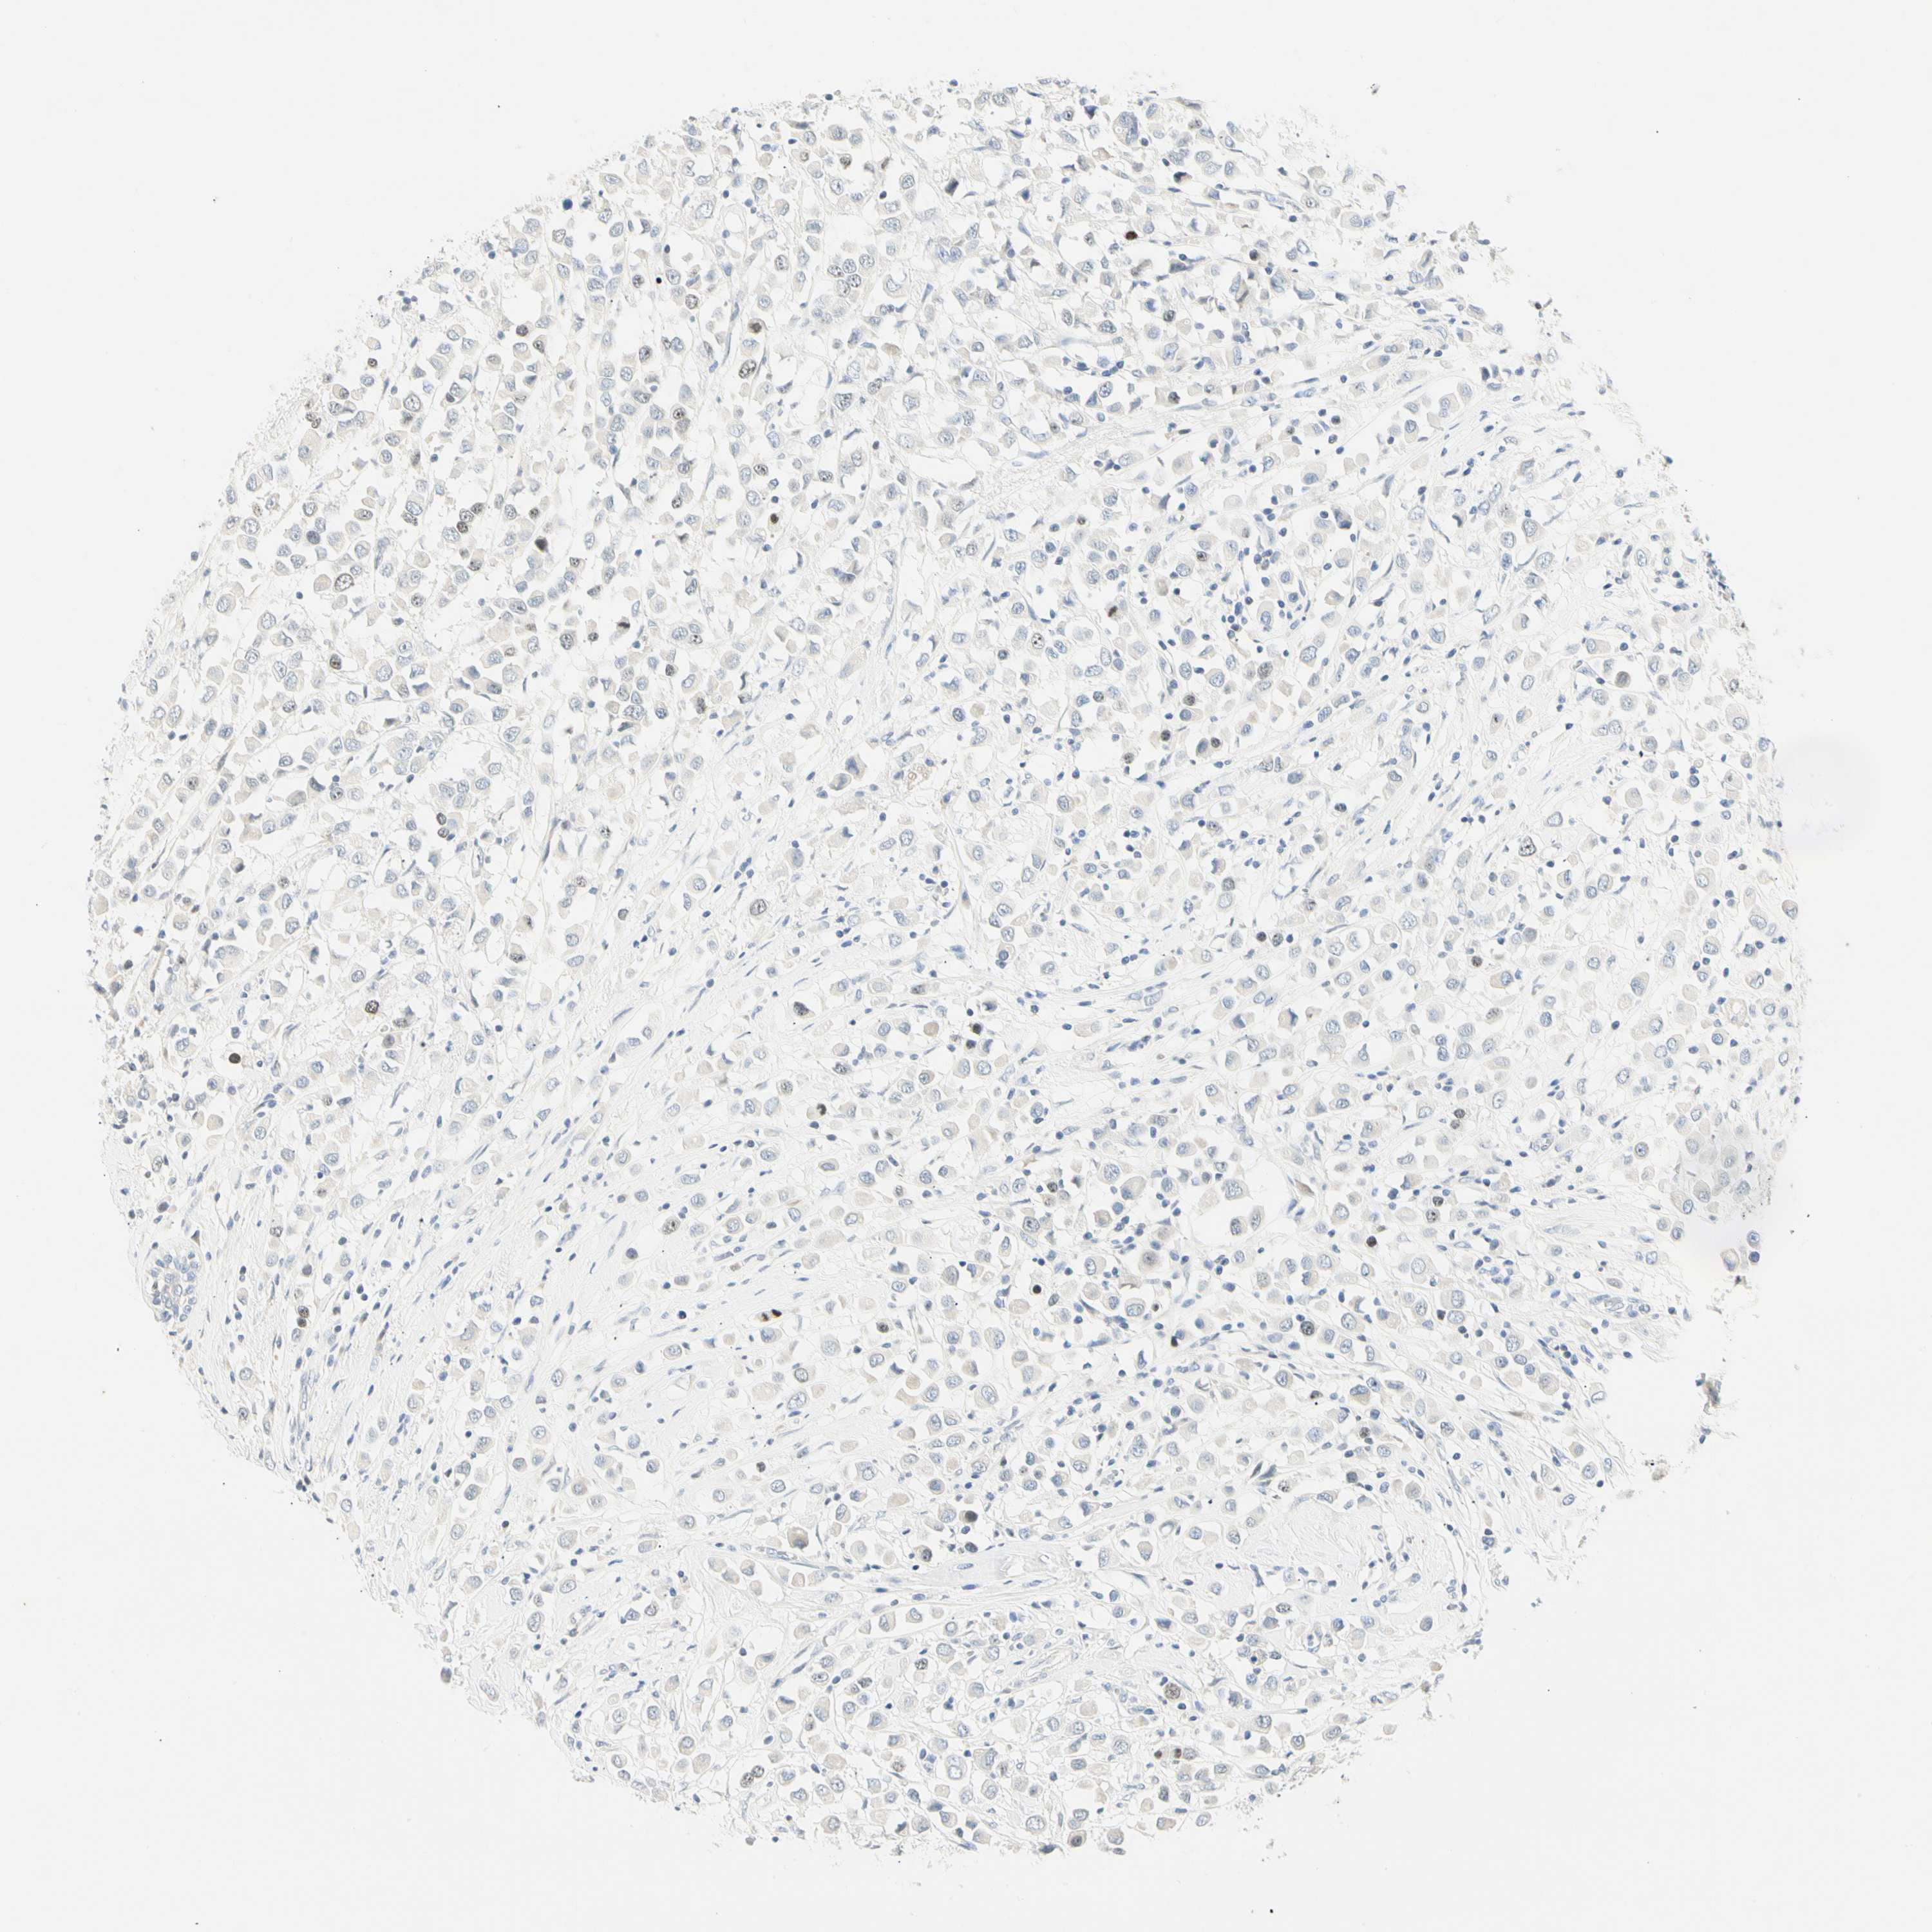

CANCER BREAST CANCER Show tissue menu

Breast cancer

Human cancer

PITX1 is not prognostic in Breast Invasive Carcinoma (TCGA)